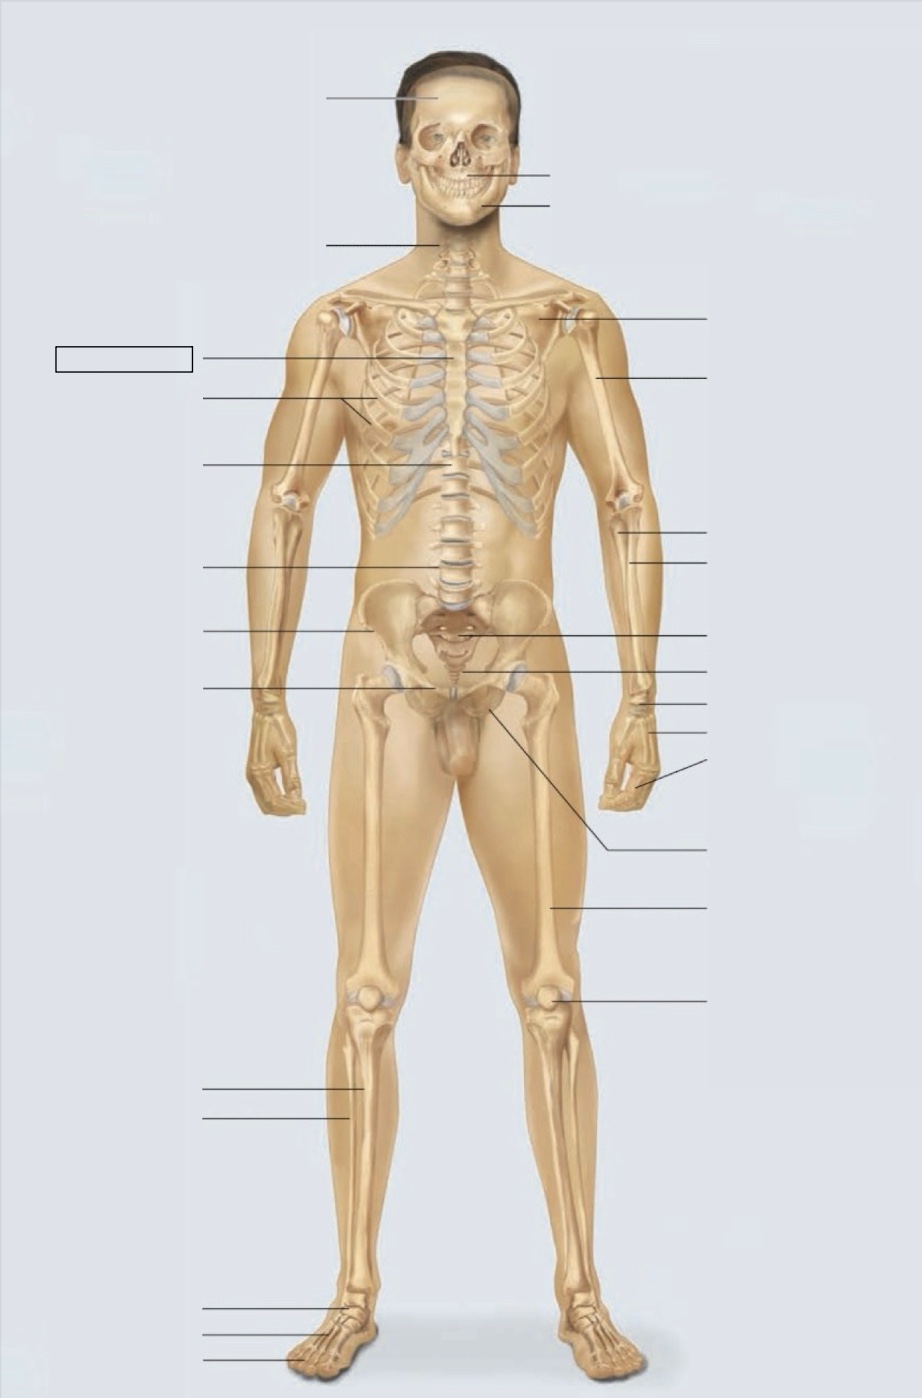

maxilla

mandible

scapula

humerus

ulna

radius

sacrum

coccyx

carpals

metacarpals

phalanges

ischium

femur

patella

phalanges

metatarsals

tarsals

fibula

tibia

pubis

ilium

lumbar vertebrae (L4)

thoracic vertebrae (T11)

ribs

sternum

cervical vertebrae

skull